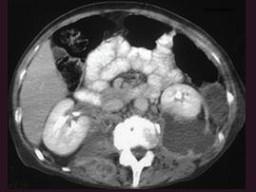

问题 男,64岁,发热,腰部疼痛半月余,请结合影像学检查,选出最可能的诊断 ( )

选项 A、脊椎骨髓瘤 B、脊椎骨髓炎 C、椎体压缩性骨折 D、脊椎转移瘤 E、脊椎结核

答案 B